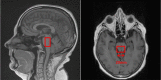

Methods and analysis: This is a prospective, single-centre, exposure/non-exposure, transverse study assessing the MRI and neuropsychological abnormalities in professional retired soccer players exposed to subconcussive impacts, compared with high-level athletes not exposed to head impacts. The primary outcome corresponds to the results of MRI by advanced MRI techniques (diffusion tensor, cerebral perfusion, functional MRI, cerebral volumetry and cortical thickness, spectroscopy, susceptibility imaging). Secondary outcomes are the results of the neuropsychological tests: number of errors and time to complete tests. We hypothesise that repeated subconcussive impacts could lead to morphological lesions and impact on soccer players' cognitive skills in the long term.